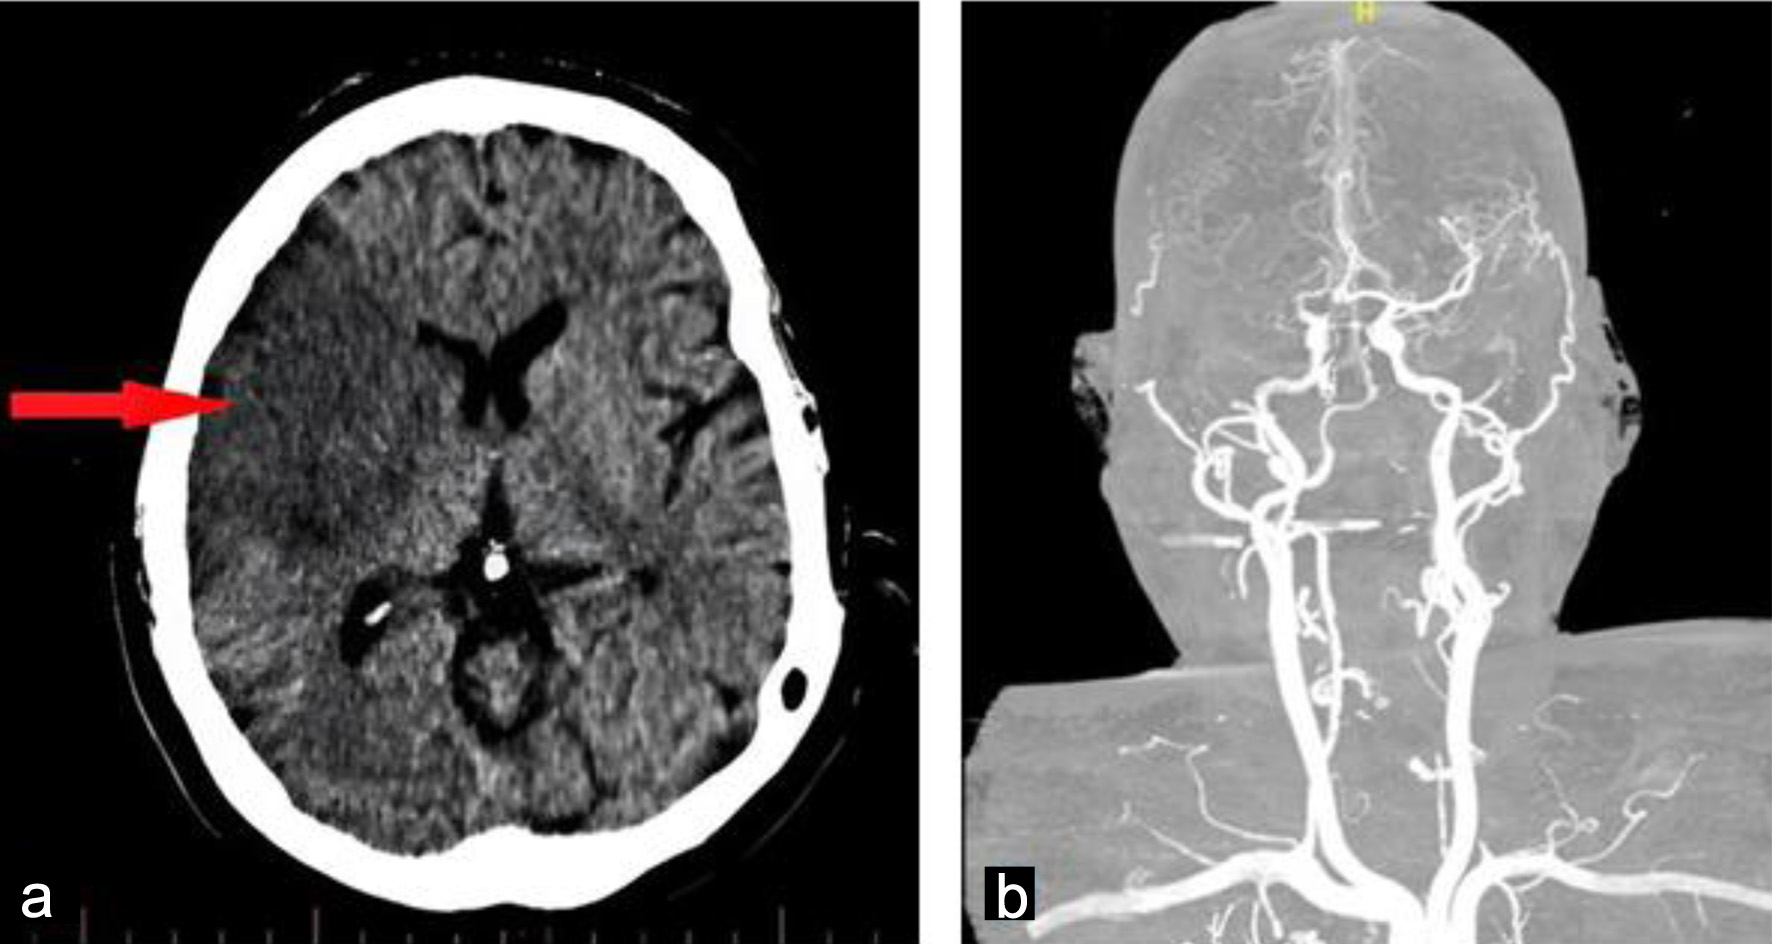

Neuroimaging was promptly performed following the onset of acute focal neurological deficits. Non-contrast computed tomography (CT) of the brain revealed a well-demarcated infarction within the right middle cerebral artery territory, consistent with an embolic ischemic stroke (Fig. 1). This finding raised immediate concern for a cardioembolic source in the context of the patient’s prosthetic aortic valve and recurrent systemic symptoms.

Figure 1. Admission brain computed tomography without contrast obtained on admission showing a well-defined hypodense lesion in the right (arrow), consistent with an acute embolic ischemic infarction (a). Cerebral angiography showed occlusion of the right middle cerebral artery (b).